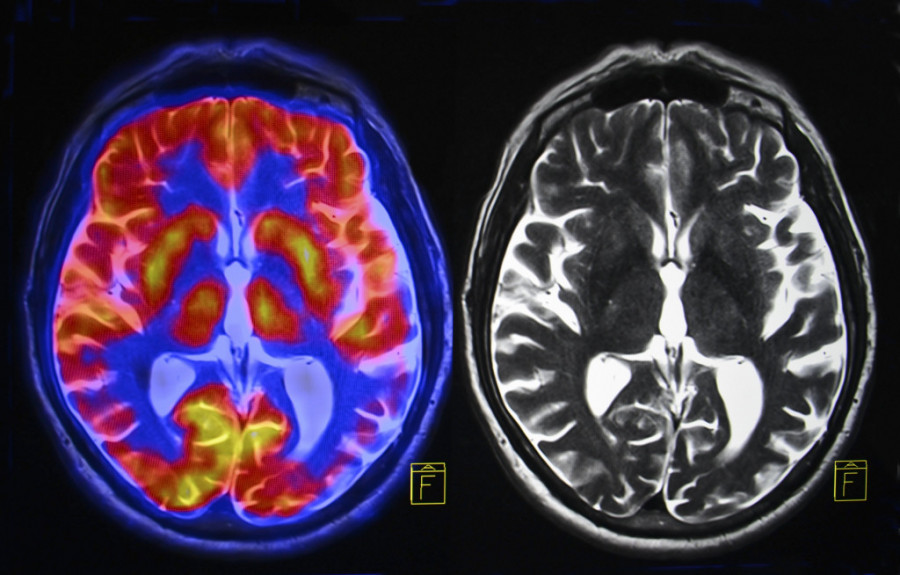

Tumor na mozgu jedne žene se gotovo povukao za manje od nedelju dana zahvaljujući "revolucionarnom" novom tretmanu.

Ova 57-godišnjakinja je videla kako njen rak nestaje za samo pet dana nakon što je bila podvrgnuta terapiji CAR-T - tretmanu koji jača imunološki sistem tela. Bila je jedan od tri pacijenta sa dijagnozom glioblastoma, te se uključila u studiju od marta do jula prošle godine.

Žena je videla "skoro potpunu regresiju tumora" nakon samo pet dana, rekli su istraživači. Dva druga pacijenta su takođe doživela smanjenje veličine tumora.

Tumor 72-godišnjeg muškarca smanjio se za više od 18 odsto posle dva dana. Do 69. dana tumor se smanjio za 60,7 odsto, a odgovor je trajao više od šest meseci.